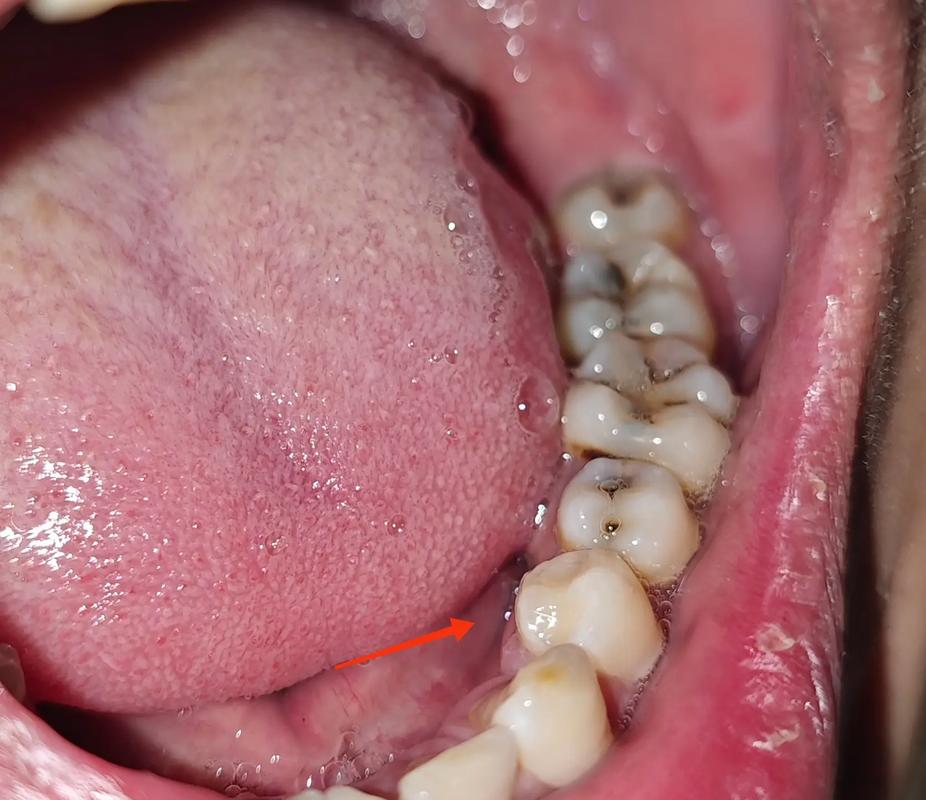

种牙拆线几天能喝酒?医生:这个时间点别碰,否则白种牙了!

作为口腔临床工作10余年的牙科专家,经常遇到种牙患者在拆线后纠结“能不能喝酒”,今天我们就从专业角度详细解答:种牙拆线后到底几天能喝酒?为什么过早喝酒会“前功尽弃”?不小心喝了怎么办? 让你避开术后“隐形杀手”,确保种牙成功!

先搞懂:拆线≠伤口完全愈合!种牙恢复分3阶段

很多患者以为“拆线=伤口好了”,其实这是个误区,种牙的伤口愈合分三个阶段,每个阶段对“刺激”的耐受度完全不同:

拆线通常在术后7-14天(具体看手术复杂度:简单种植拆线7天,骨增量等复杂手术可能10-14天),此时伤口表面虽然缝线拆除,但深层组织(牙槽骨、种植体周围)仍在愈合,属于“假性愈合”——表面看着结痂,内部还很脆弱。

术后4周-3个月:骨结合关键期

种植体要和牙槽骨“长在一起”(医学叫“骨结合”),这是种牙成功的核心!这个阶段骨细胞正在活跃增殖,任何不良刺激都可能让骨结合失败。